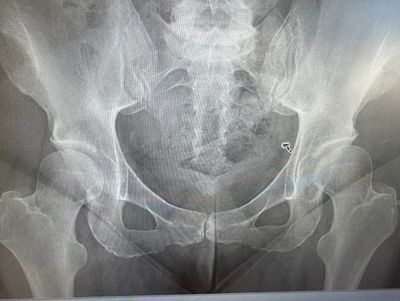

Many patients who have missed dysplasia have previously had an x-ray, which was reported as normal or no bony abnormality seen or no OA. My advice is to always review the x-ray image yourself and complete some of the simple angles such as Lateral centre edge angle (LCEA), Sourcil angle or Acetabular index (AI), as well as look for signs such as cross-over sign or ischial spine sign which may indicate retroversion.